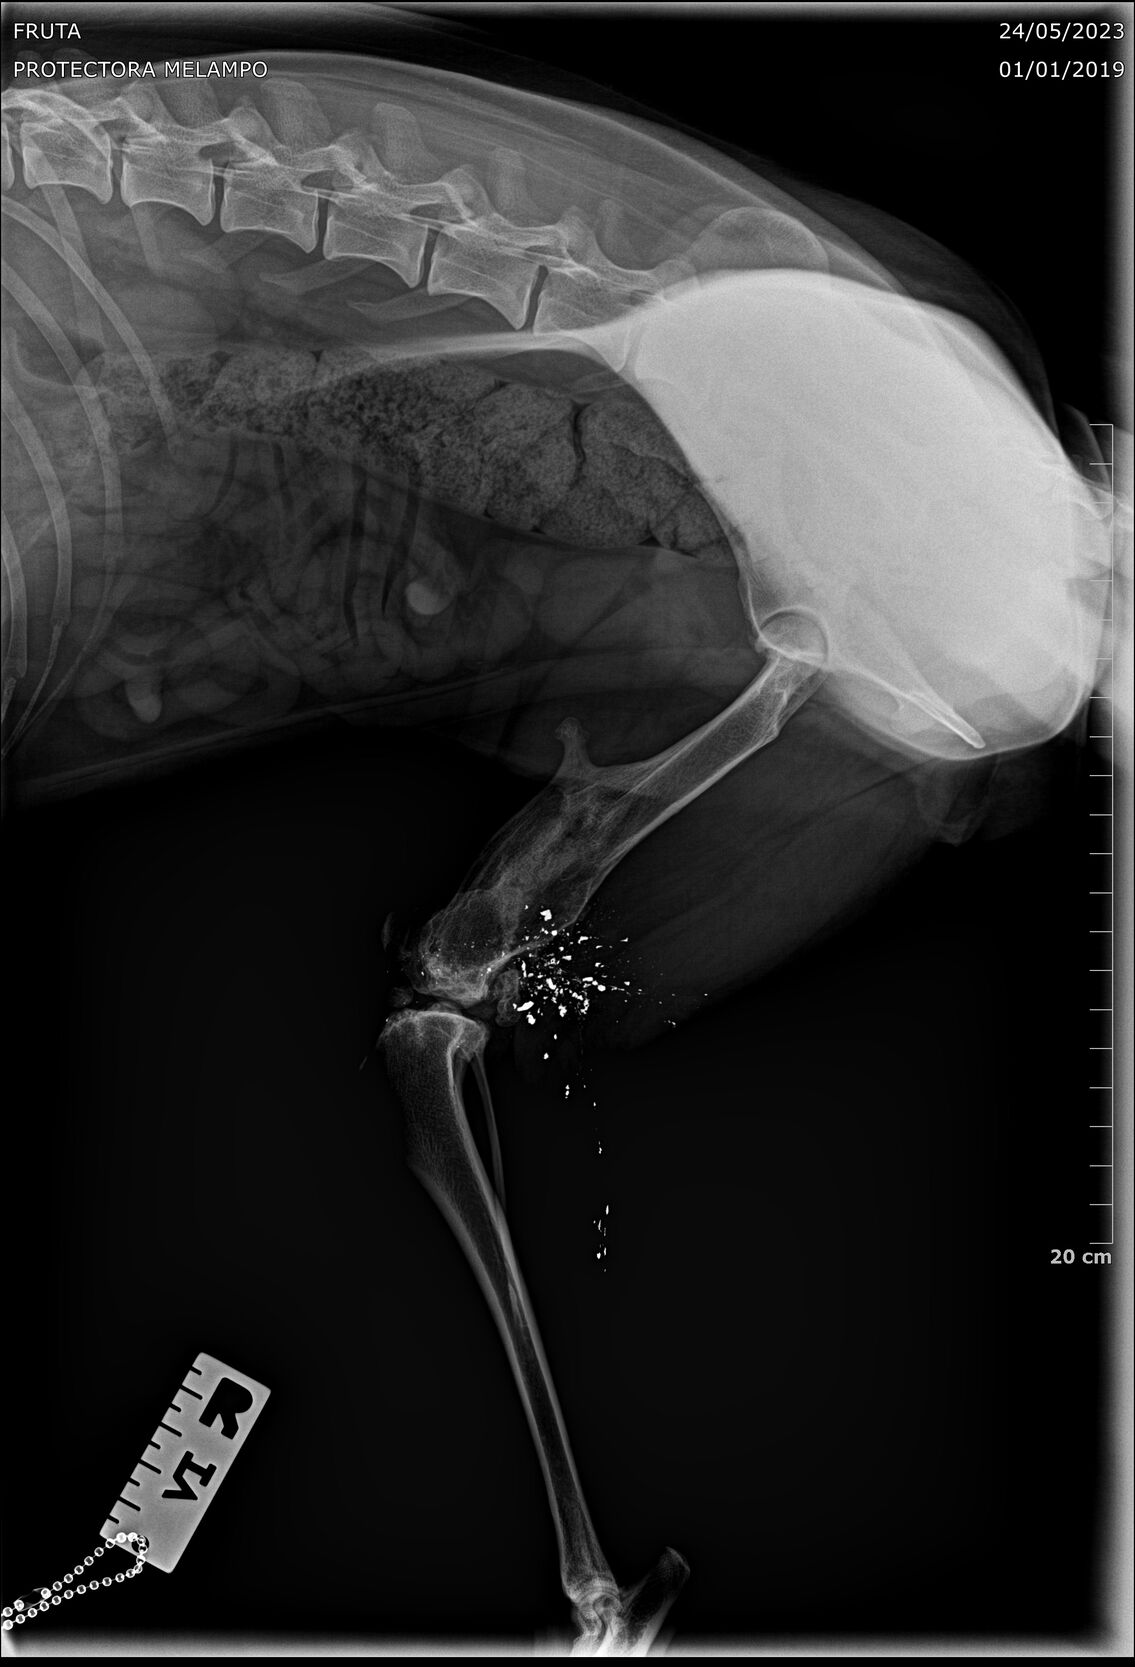

Update 26.05.2023

Fruta wurde kastriert und ihr alte Verletzung wurde dabei auch gleich geröngt. Dabei kam heraus, dass Fruta eine Schussverletzung hat und immer noch Schrot im Bein hat. Die Röntgenbilder sind weiter unten zu finden.

Fruta’s Hinterbein wurde beim Spezialisten abgeklärt. Das Bein ist steif, sie hat aber keine Schmerzen. Es stört sie auch nicht, sie läuft, rennt und hüpft auch ohne Probleme aufs Sofa.